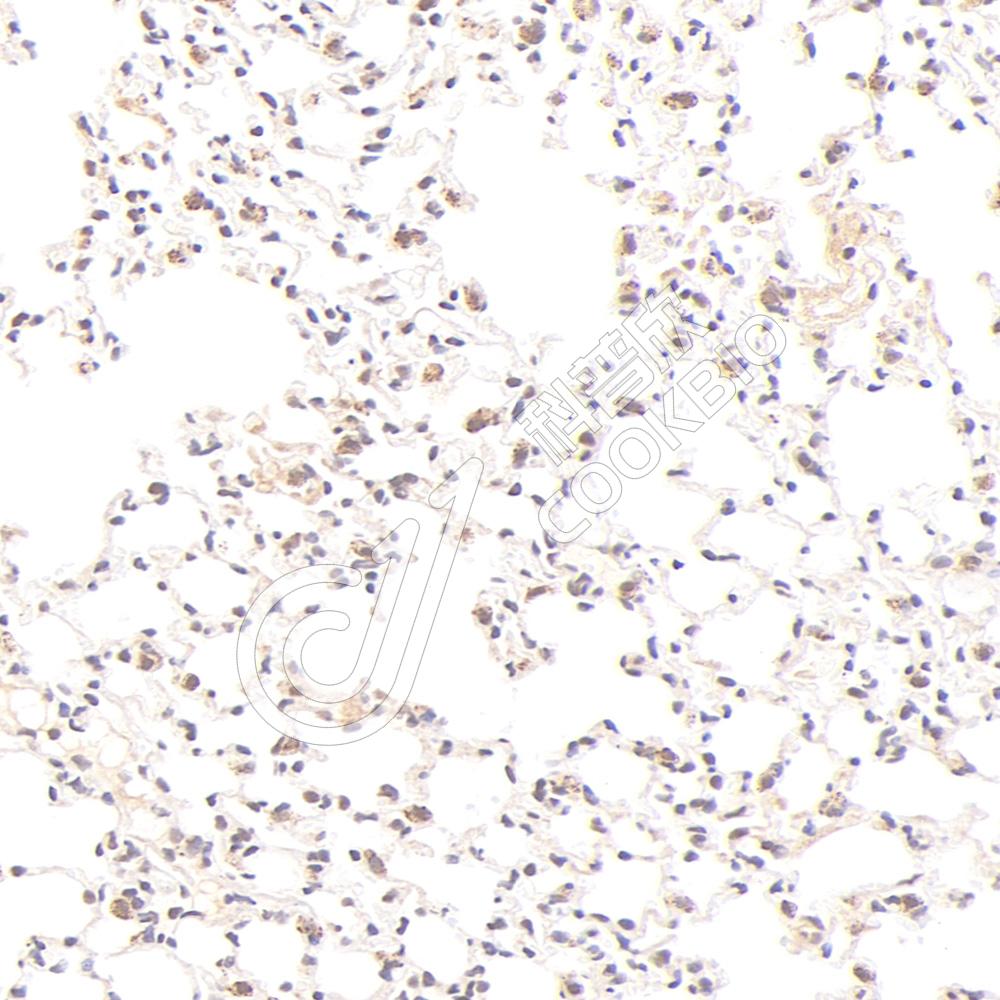

IHC检测LYNX1蛋白(货号 K1345789).

样品: 大鼠脑, 4%多聚甲醛 (货号KSG1101) 固定12-24小时.

抗原修复: Tris-EDTA抗原修复液(pH 9.0) (KSG1203), 98℃, 20分钟.

—抗: 1: 1000稀释, 4℃ 孵育过夜.

二抗: S-vision免疫组化多聚二抗(山羊抗兔),即用型 (货号KB3906), 室温孵育20分钟.